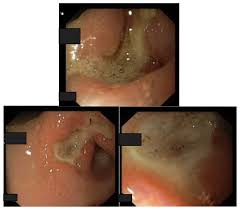

67 years old Gender. Clinical Study of Peptic Ulcer Disease Peptic ulcer disease refers to painful sores or ulcers in the lining of the stomach or first part of the small intestine called the duodenum. Aggressive factors-bile acid and pepsin Defensive factors-mucus bicarbonates and PG.

Peptic ulcer - is a circumscribed loss of the mucus membrane of the GIT system exposed to gastric juices containing acid pepsin. Rivera RN Peptic Ulcer Disease PUD is a term used to describe a group of ulcerative disorders that occurs in areas of the gastrointestinal tract that are exposed to acid-pepsin secretion. However evidence-based research points that these cases of morbidity and mortality have substantially fallen thanks to the.